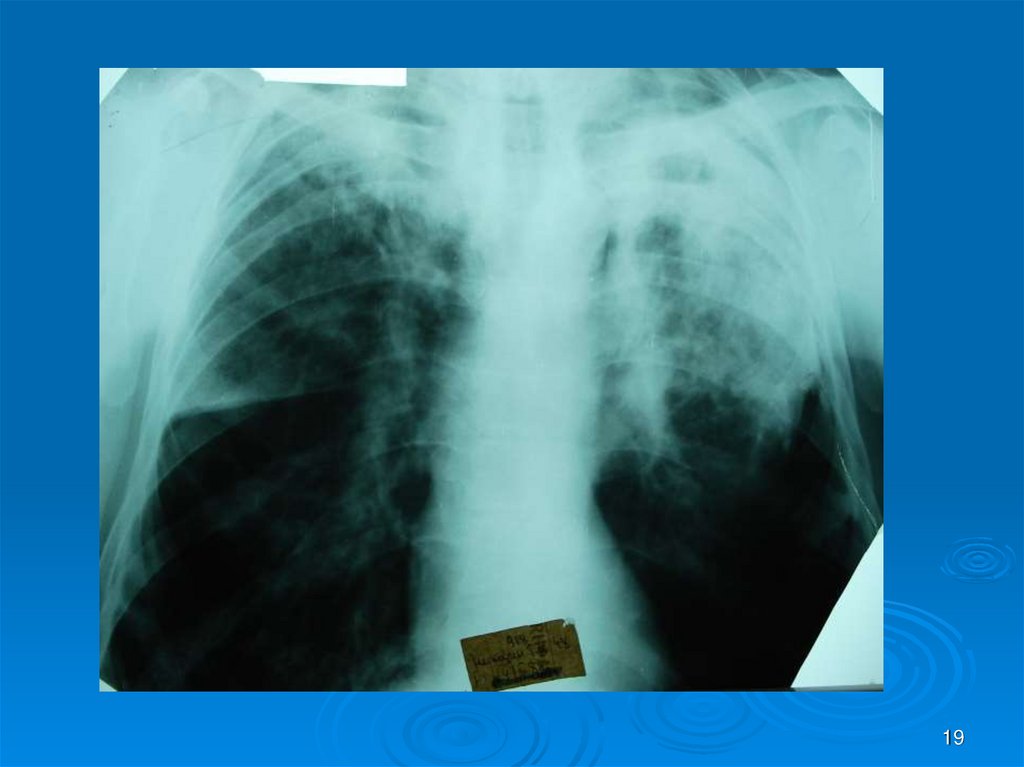

19.

19